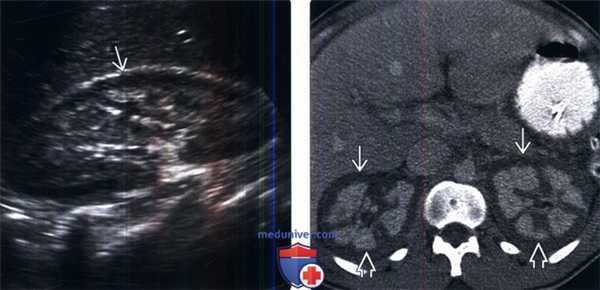

(Слева) УЗИ правой почки в продольной плоскости: у пациента с серповидноклеточной анемией и кортикальным некрозом выявлена сниженная эхопенность коркового слоя почки по сравнению с мозговым слоем.

(Справа) КТ с контрастированием, аксиальная проекция: у того же пациента выявлены двустороннее отсутствие накопления контраста корковым слоем почки и сохранение контрастирования мозгового слоя, что соответствует двустороннему некрозу коркового слоя почек.